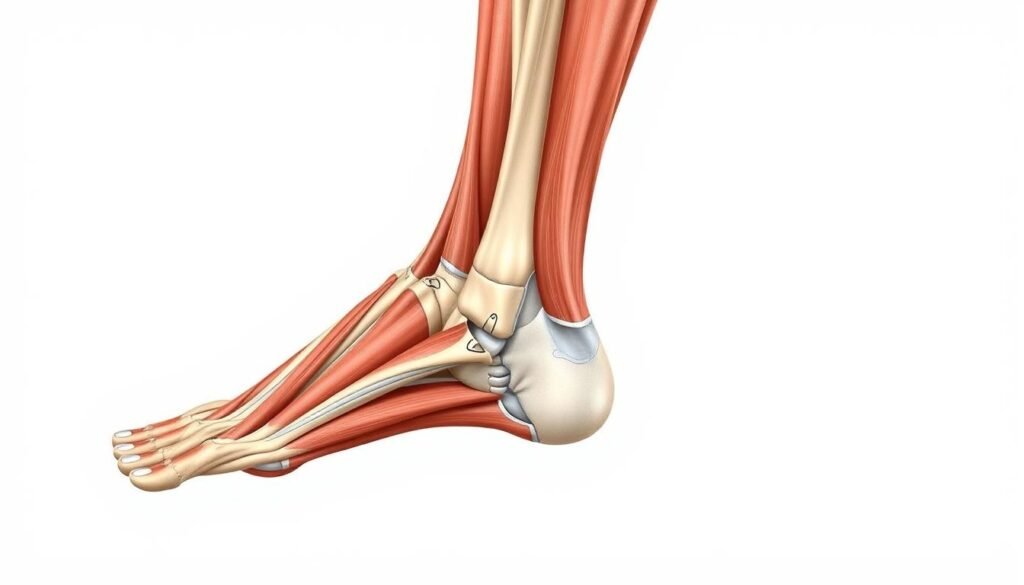

Jakie mięśnie pracują podczas ćwiczeń na łydki?

Podczas ćwiczeń na łydki pracują różne grupy mięśniowe. Zrozumienie, które mięśnie są zaangażowane, pomaga osiągać lepsze wyniki. Przyjrzyjmy się bliżej tym mięśniom.

Mięśnie trójgłowe łydki

Mięśnie trójgłowe łydki składają się z mięśnia brzuchatego i płaszczkowatego. Mięsień brzuchaty pomaga zgiąć kolano i stopę. Ważne jest, aby ćwiczyć obie głowy mięśnia brzuchatego.

Warto skupić się na pełnym ruchu. To przyniesie lepsze efekty.

Mięśnie piszczelowe

Mięśnie piszczelowe mają kluczową rolę. Stabilizują stopę i pomagają zachować równowagę. Silne mięśnie piszczelowe są ważne dla codziennych ruchów.

Regularne ćwiczenia, takie jak chód na palcach, pomagają w ich rozwoju.